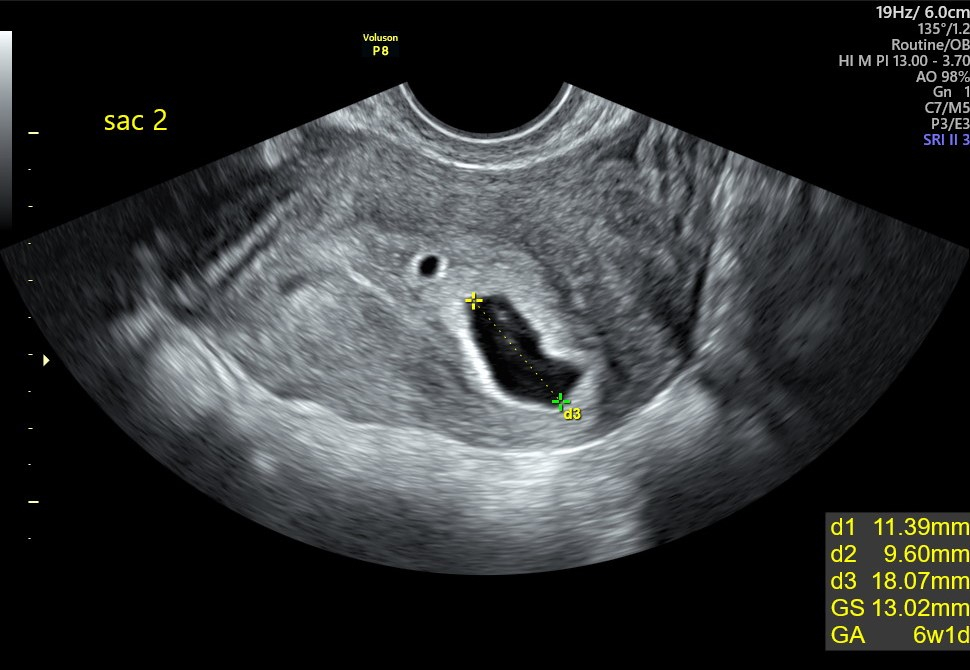

I am currently 7wks today. This is my first successful pregnancy after our 2nd embryo transfer. Went in for our first US on Monday. The nurse found 2 gestational sacs with only one looking promising. Even though I was 6wk4d going in, the sac measured 6wk1d. Unfortunately, they didn't find the yolk sac or fetal pole and stated it could be too early. The US to me didn't look entirely empty but I'm not an expert. My fertility doctor called with her opinion and stated that she was concerned that she didn't see the growth that "She" expected in the US and felt that we were behind. She then goes on to say that she feels that this may not be a viable pregnancy but to make an appointment next week and she'll be praying for us. Not a good feeling AT ALL. DH and I have been crying since then as we have waited a long time (3 years) for this moment. I now have period-like cramps that feel like my actual period is about to come on but no bleeding. My belly was a little tender before whenever I would get up from sitting but now it's not as tender since the US. Still using the bathroom every 1 or 2 hours. And my breast seems less tender than before. So I feel like my symptoms are subsiding. :'(